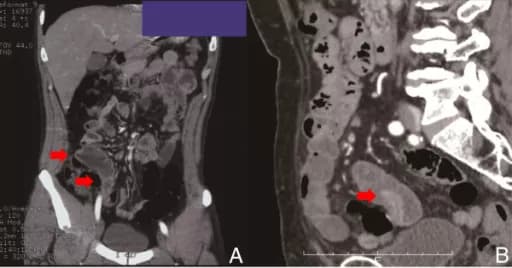

Technetium scan or a Meckel’s scan: The scan procedure consists of injecting into the veins, a liquid with small amounts of radioactive molecules in it, called Technetium-99m. A camera, called a gamma camera, is used to take pictures of the abdomen after the liquid has been injected. The test will indicate the presence of rectal bleeding, one of the signs of Meckel’s Diverticulum.